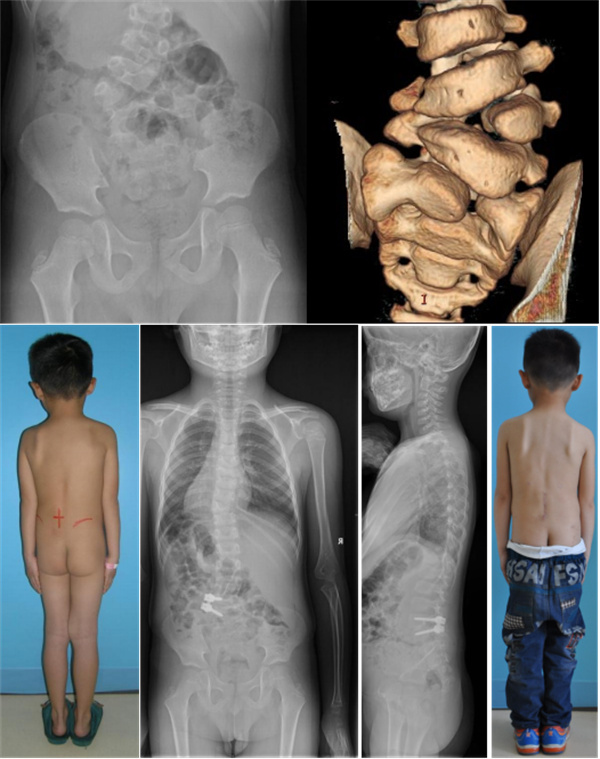

小儿腰骶段半椎体

患者先天性脊柱侧凸,椎体发育异常,位置较低,年龄较小。术中半椎体及椎间盘需彻底切除,髂血管损伤风险较大。患者年龄小,骨质软,术中内固定极易松动。手术时间长,出血多,术中低体温,术后感染等风险较大。